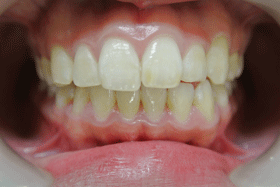

一度も虫歯になってない口腔内